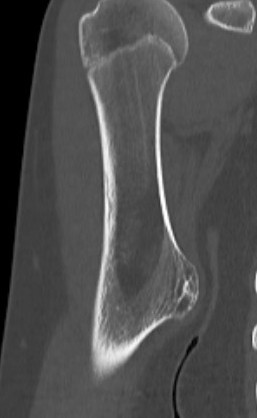

CT

Cortex and medullary cavity of normal bone contiguous with osteochondroma

Cortical and marrow continuity

Types

1. Pedunculated - has a stalk, points away from joint

2. Sessile - attaches to bone with a broad base

Pedunculated

Protuberant bony lesion arising adjacent to physis

- directed away from joint

- cortical bone and marrow space continuous

Sessile